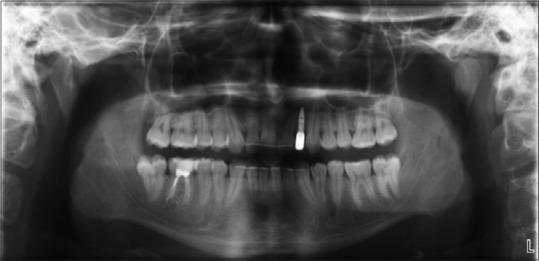

Bone defects at the anterior regions of the jaws often cause esthetic problems such as gingival disharmonies and longer crowns than neighboring teeth. Variety of procedures can be used in this region for achieving sufficient bone volume with or without different bone graft materials. All of these procedures has their own advantages and disadventages. New bone formation was defined with orthodontic tooth movement in different regions. In this case we present the use of orthodontic tooth movement, for achieving sufficient bone volume, in anterior maxillary region, for esthetic and functional results.

颌骨前部的骨缺损常常会导致美观问题,如牙龈不协调以及牙冠比相邻牙齿长。在该区域可采用多种方法,无论是否使用不同的骨移植材料来获得足够的骨量。所有这些方法都有其自身的优缺点。在不同区域,正畸牙齿移动可促进新骨形成。在此,我们介绍在前上颌区域利用正畸牙齿移动来获得足够的骨量,以实现美观和功能效果。